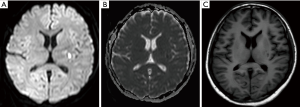

Routine laboratory tests were unremarkable, including liver and renal function, thyroid function, immunologic tests and serum ceruloplasmin level. The exception was a slightly elevated fasting serum glucose level (125 mg/dL). Transthoracic echocardiography was normal, and 24-hour Holter monitoring did not show arrhythmia. Subsequent brain magnetic resonance imaging at 3.0 T revealed acute ischemic stroke involving the left putamen (Figure 2) and periventricular area. However, magnetic resonance angiography did not show any stenosis in the left middle cerebral artery (Figure 3). Diffusion tensor imaging of the brainstem and cervical spine revealed normal cortico-spinal tract decussation in the lower medulla oblongata (Figure 4). The patient was diagnosed with acute onset post-stroke hemiballism that induced MM in her unaffected limb. She was given one week of clonazepam and haloperidol therapy, after which MMs and hemiballism nearly disappeared (Figure 5). The patient was discharged with standard ischemic stroke prevention measures including aspirin and atorvastatin. At follow-up 1 year later, no further episodes of involuntary movement had occurred.